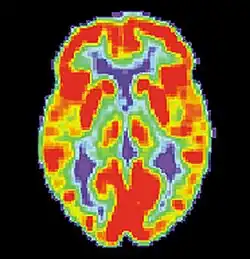

Los sistemas neuronales utilizados por la memoria procedimental suelen verse afectados por el virus de inmunodeficiencia humana, siendo el estriado la estructura más notablemente afectada.[46] Los estudios realizados con resonancia magnética de imágenes han detectado irregularidades en la sustancia blanca y atrofia subcortical en los ganglios basales, áreas vitales para la memoria procedimental y el aprendizaje de habilidades motoras.[47] en diversas tareas de memoria procedimental utilizadas en investigación aplicada, como la prueba de persecución rotatoria, el dibujo en el espejo y la predicción del tiempo, se encuentra que los pacientes de VIH positivo se desempeñan peor que los VIH negativos, lo que sugiere que estos empobrecimientos en la ejecución de las tareas se deben a cambios cerebrales específicos ocasionados por la enfermedad.[48]